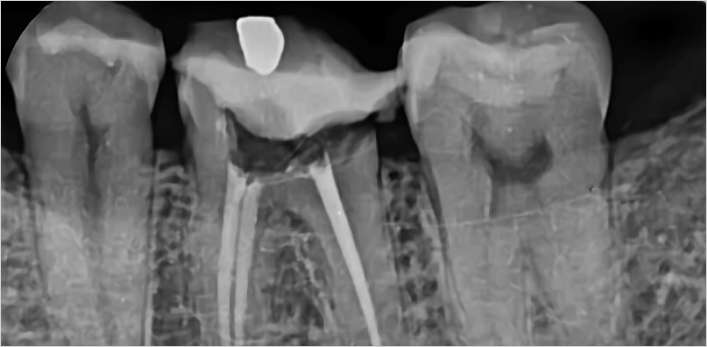

김** 환자분 (신경치료 진행 후 지르크라운으로 치료)

왼쪽아래 어금니 통증으로 방문,

보철물 제거 후 확인해보니 남은 치질이 별로 없어 post 추가 및 신경치료 진행 후 지르크라운으로 치료

위 치료 사례는 서울스마트치과에서 직접 치료를 받고, 환자 본인의 동의를 얻어 게재된 사진으로 무단 인용, 도용, 재배포 시 민/형사상 책임을 질 수 있습니다.